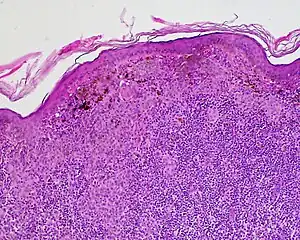

Halo nevus (also known as "Leukoderma acquisitum centrifugum," "Perinevoid vitiligo," and "Sutton nevus"[1]: 689 ) is a mole that is surrounded by a depigmented ring or 'halo'.

Halo nevi are also known as Sutton's nevi, or leukoderma acquisitum centrifugum. Halo nevi are named such because they are a mole (nevus) that is surrounded by an area of depigmentation that resembles a halo.

The formation of a halo surrounding a nevi is believed to occur when certain white blood cells called CD8+ T lymphocytes destroy the pigment-producing cells of the skin (melanocytes).[2] The cause for the attack is unknown.[3]